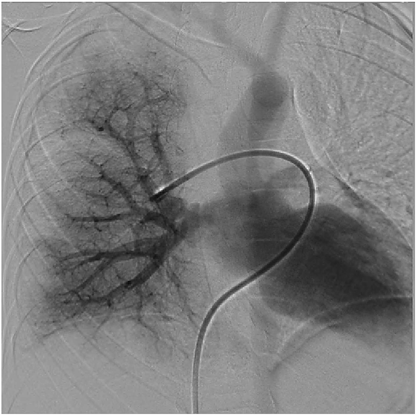

Fig. 5 Right pulmonary artery angiography demonstrated smooth right pulmonary venous flow at 1 year postoperatively in case 1